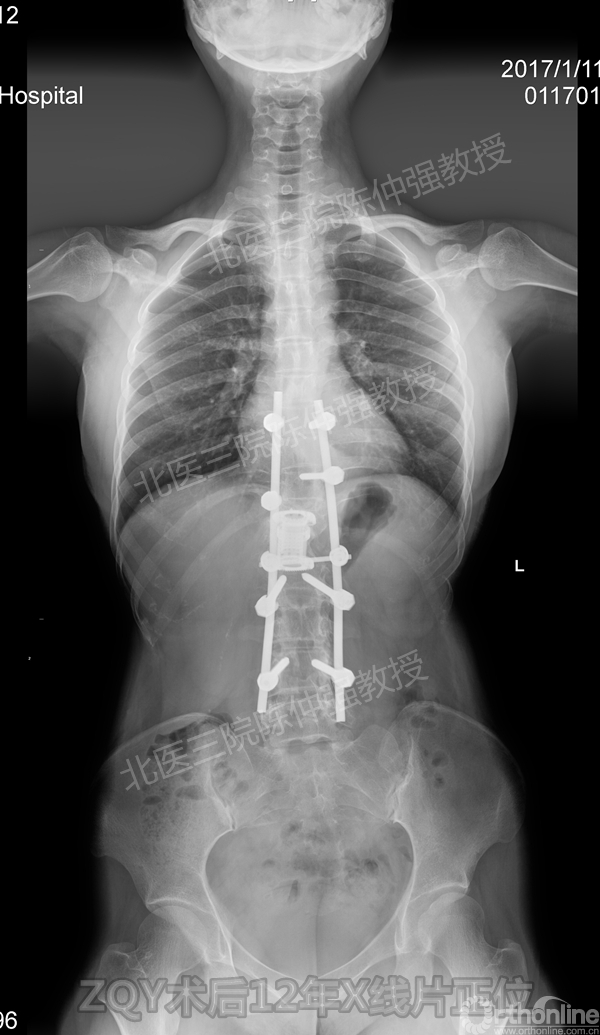

ZQY术后12年

患者女性17岁,胸腰椎陈旧结核性侧后凸畸形,局部呈“麻花状”扭转,无神经功能受损表现。2005年,陈仲强教授带领团队实施后路+侧前方联合入路脊柱节段切除、双轴旋转矫形术。术后患者外观显著改善,神经功能正常。术后随访证实患者截骨矫形节段骨性融合良好,矫形效果持续良好。